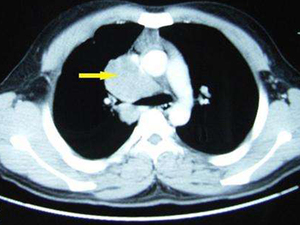

(3)肺部肿瘤压迫引起的纵隔移位往往在CT上纵隔旁发现占位性病变,恶性结节或团块常不规则,边缘可有毛刺,多呈分叶状。可同时伴肺内转移性结节病灶。